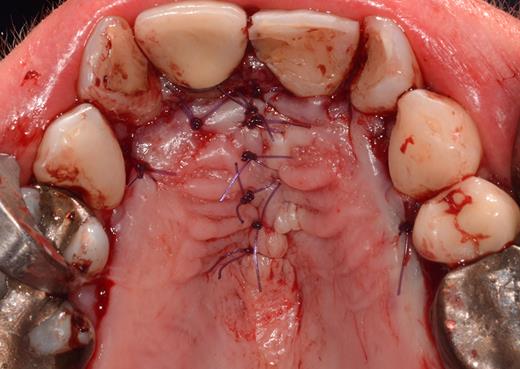

After a sulcular incision on the palatal side from teeth 15 to 25 and an incision in the midline of the palate omitting the incisive papilla and the two orifices of the NPD, two full-thickness mucoperiosteal flaps were raised. Thereafter, the incisive papilla and the whole contents of the incisive canal were enucleated (Figs 4–6). The bony incisive canal was filled with autologous bone harvested from the palatal region (bone scraper) (Fig. 7). A tension-free primary wound closure was achieved by moving the palatal flaps to the midline using single button and interdental vertical mattress sutures (Monocryl 4-0, Ethicon, Johnson & Johnson, USA) (Fig. 8). To avoid wound dehiscence and hematoma, an iodoforme gauze and a palatal plate were applied (Fig. 9). The patient was instructed to rinse three times a day with 0.1% chlorhexidine (formula hospitalis) for 2 weeks postoperatively. Sutures were removed after 14 days.

Filling of the incisive canal using autologous bone harvested from the palatal region.